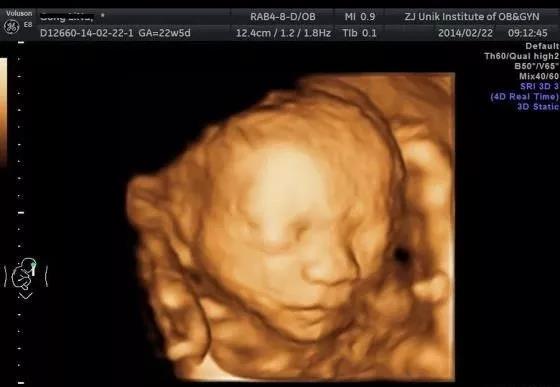

第三次,20 ~ 24孕周

此时胎儿的复杂器官如心脏和大脑已经发育好,是进行系统性超声检查排查畸形的最佳时期。检查内容包括胎方位、胎心搏动、胎儿生物学测量,对胎儿的大脑、颜面部、颈部、胸部、心脏、膈肌、腹部、脊柱、四肢全面观察,还包括胎盘、脐带、羊水量的检查,筛查六大致死性畸形和各主要器官的畸形。这是产前超声检查中最重要的一次,一般需要30~45min,各位孕妈需要提前预约好,以免错过最佳时期。